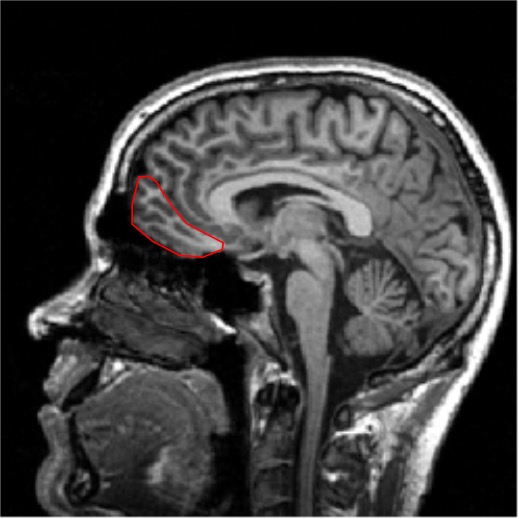

Gustatory cortex

- Primary somatosensorycortex (Postcentral gyrus)

- Gustatory Cortex (frontal operculum andanterior insular cortex)

- Fronto-parietal operculum

- Lateral sulcus

- Insular cortex

- fig origin unknown.

Note that the gustatory cortex is very close to the tongue area on the somatosensory cortex!

Cortical projections of gustatory pathway

From the VPM projections reach the gustatory cortex: anterior insular cortex and frontal operculum.

Information derived from different areas of the tongue is spatially segregated in the n. of the solitary tract, the thalamus, and the cortex. (Still true?)